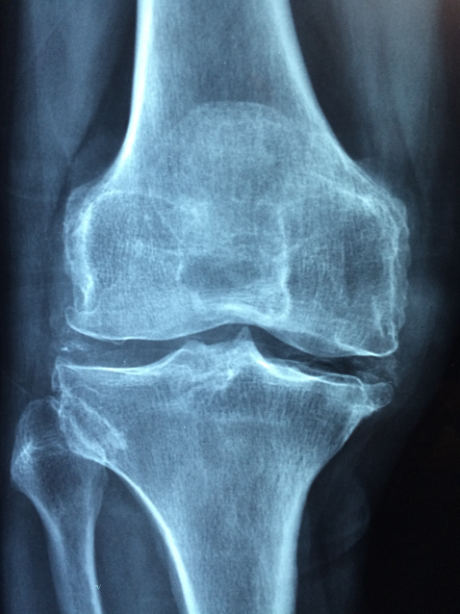

골관절염(osteoarthritis)은 관절 연골과 그 밑에 경골조직의 손상으로 생기는 질환이다. 관절염에는 류마티스성 관절염도 있지만 관절염으로는 골관절염이 가장 흔한 형태이다. 관절이 아프고 경직되는 증세가 나타나며 처음에는 움직일 때에 한해 통증을 느끼지만 만성이 되면 지속적으로 통증을 느끼게 된다. 나이가 들 수 록 많이 발병하며 전 세계적으로 수백만 명이 이 병으로 고생하고 있다. 한번 발병하면 계속 진행되는 대표적인 퇴행성 질환이다.

골관절염은 전 세계 수백만 명의 사람들에게 영향을 미치는 현재의 피로한 질환입니다. 일반적인 연골이 점진적으로 파괴되어 통증, 경직, 운동성 저하로 이어지는 것이 특징인 관절염의 한 형태입니다. 이 블로그 게시물에서, 우리는 골관절염의 원인, 증상, 그리고 치료 방법을 면밀히 조사할 것이며, 이 상태를 관리하고 삶의 질을 향상할 수 있는 소중한 통찰력을 제공할 것입니다.

II. 골관절염 증상 인식하기 :

골관절염은 주로 관절에 영향을 미치며, 증상은 사람마다 다를 수 있습니다. 다음은 일반적으로 주의해야 할 몇 가지 징후입니다:

a) 관절 통증 및 뻣뻣함:

특히 활동을 하지 않거나 과도하게 사용한 후에는 영향을 받는 관절의 통증과 경직이 골관절염의 일반적인 증상입니다. 통증은 움직임에 따라 악화되고 휴식에 따라 개선될 수 있습니다.

b) 감소된 동작 범위:

연골이 악화되면 관절의 유연성이 떨어져 운동 범위가 줄어들 수 있습니다. 이것은 구부리거나 들어 올리거나 계단을 오르는 것과 같은 일상적인 활동을 수행하는 것을 어렵게 만들 수 있습니다.

c) 관절의 붓기와 부드러움:

관절에 염증이 생기면 붓기와 압통이 생길 수 있습니다. 영향을 받는 관절은 접촉 시 따뜻함을 느낄 수 있으며 눈에 띄게 부어 보일 수 있습니다.